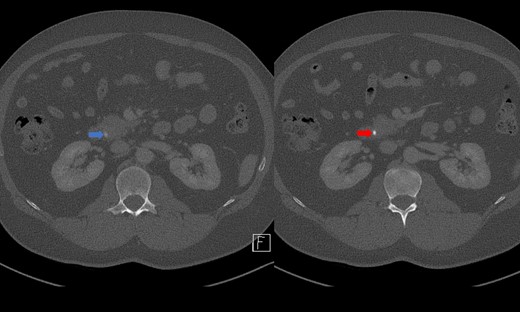

Endoscopic retrograde cholangiopancreatography (ERCP) was performed on day three of admission. Following CBD cannulation and sphincterotomy, balloon trawl of the duct was performed yielding a large volume of chalky, granular material with detritus and stones; confirming a diagnosis of LBS (Fig. 3). A stent however could not be placed as the gravelly material blocked the channel of the endoscope. Therefore, the obstructing calculus in the distal CBD was not obviously removed hence the recommendation was for intraoperative cholangiogram (IOC) to be performed at laparoscopic cholecystectomy to confirm if a filling defect remained in keeping with a calculus.

Intraprocedural images during ERCP demonstrating chalky limy bile.